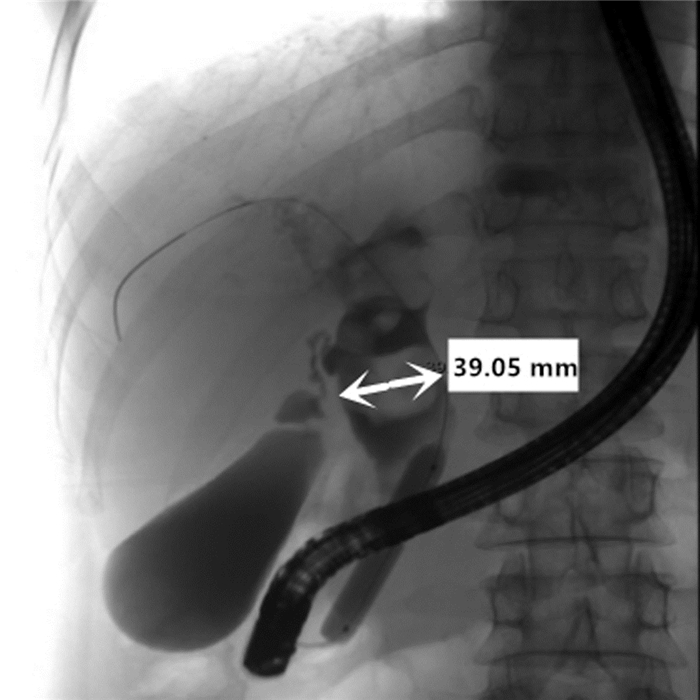

Efficacy and safety of SpyGlass system combined with electrohydraulic lithotripsy during endoscopic retrograde cholangiopancreatography in treatment of difficult common bile duct stones

Yijun LIU, Qiao WU

2021, 37(7): 1644-1647. DOI: 10.3969/j.issn.1001-5256.2021.07.032

Abstract(1695) HTML (655) PDF (2277KB)(79)

Abstract:

Objective  To investigate the efficacy and safety of SpyGlass system combined with electrohydraulic lithotripsy during endoscopic retrograde cholangiopancreatography (ERCP) in the treatment of difficult common bile duct stones.  Methods  A total of 20 patients who used the SpyGlass system combined with electrohydraulic lithotripsy during ERCP for the treatment of difficult common bile duct stones in Department of Hepatobiliary Surgery, The First Affiliated Hospital of Chongqing Medical University, from December 2019 to May 2020 were enrolled. Liver function, blood amylase, and blood lipase were measured after surgery; the patients were observed in terms of body temperature, abdominal pain, hematobilia, infection, and perforation; the presence or absence of residual common bile duct stones was reexamined after surgery.  Results  Of all 20 patients, 18 underwent successful lithotripsy on the first attempt without serious complications, and 2 underwent ERCP-guided basket extraction and biliary tract cleaning with balloon due to residual stones found in the reexamination after surgery and achieved complete removal of stones. No biliary tract perforation or massive hemorrhage was observed; there was mild pancreatitis after surgery, which was improved after pharmacotherapy; some patients had increased levels of blood amylase and lipase, without any clinical symptom; there was a significant improvement in liver function after surgery. Abdominal color Doppler ultrasound performed for all patients at 3 months after cholecystolithotomy showed no residual common bile duct stones.  Conclusion  SpyGlass system combined with electrohydraulic lithotripsy during ERCP has a high first-attempt success rate of complete removal of stones in the treatment of difficult common bile duct stones, without marked surgical complications.